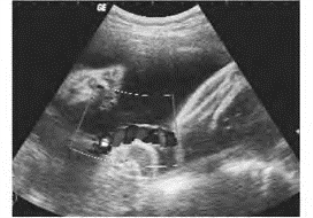

(1)脐带与胎儿后颈部纵向交叉走行,于颈后见数个小的暗淡区,彩色多普勒显示为动、静脉血流频谱,有的胎儿颈后皮肤出现“U”形压迹。

(2)横切面扫查胎儿颈部,可显示“V”或“O”形状的脐带彩色血流(图34-23)。